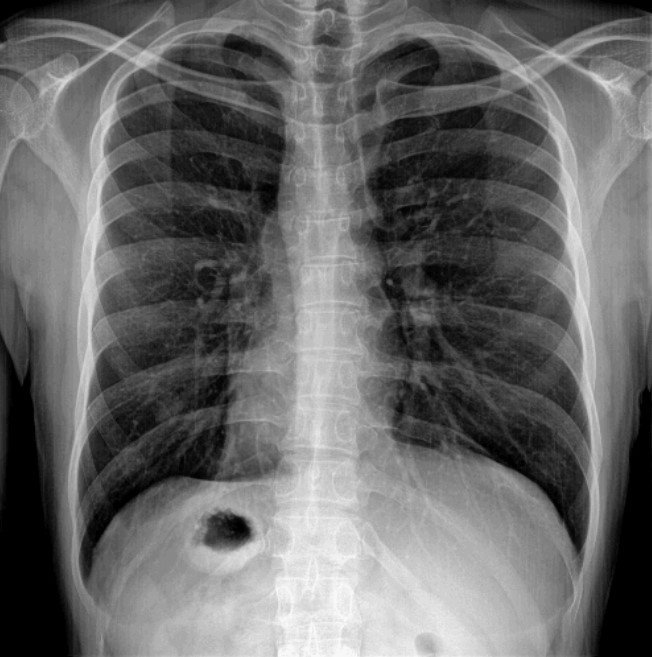

DR和X光机的区别是,DR是在普通X光拍片的基础上,发展成为数字化X线拍片。DR拍片检查也是需要利用到X线,虽然检查的部位和普通X光拍片都是 样的,但图像的分辨率高多了,放射线辐射剂量也降低了非常多。DR相比较普通的X光拍片,图像能接入医院的网络传输,储藏系统,这样临床医生就可以在自己的电脑终端调取图像, 大的提高了工作的效率。

普通X光机和DRX光机整体上几乎没有差别,主要的差别是在成像系统上,普通X光机使用的成像方式为普通胶片或者增感屏,而DR类X光机使用的成像方式,都是使用数字平板探测器,采集到射线,把射线转变成电信号,探测器把电信号在转变成数字信号,终在显示器端展示出来,供医生诊断或者打印图片。